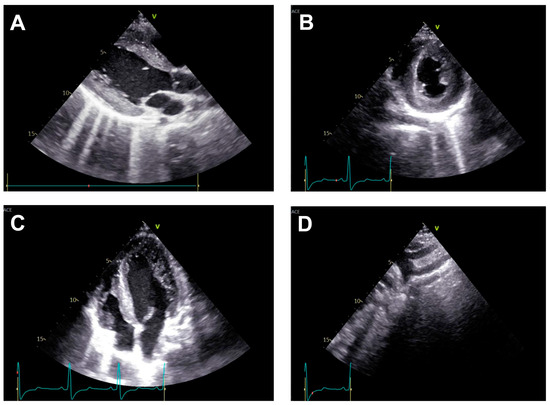

Transthoracic echocardiography (Figure 2) may reveal signs of left ventricular hypertrophy and diastolic dysfunction from the apical and parasternal views, while the suprasternal view may identify the aortic atretic segment. However, the presence of collateral circulation is difficult to identify using this technique [21].

Angio CT (CT angiography) is typically performed at specific intervals after aortic coarctation repair with stent implantation to assess stent position, vessel patency, and rule out complications such as restenosis, aneurysm, or stent migration. Angio CT is usually recommended within the first 1–3 months after stent placement to verify correct stent expansion, position, and absence of immediate complications. After the initial scan, repeat angio CT or MRI is generally performed at 6–12 months after intervention to monitor for restenosis, vessel remodeling, or aneurysm formation. The choice between angio CT, MRI (preferred in younger patients due to lack of radiation), or echocardiography depends on age, stent type (metal artifacts), and clinical scenario [33] (Figure 5).